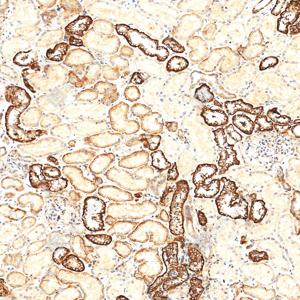

| IHC检测LRP1蛋白(货号 GB155473). 样品: 人肾, 4%多聚甲醛 (货号G1101) 固定12-24小时. 抗原修复: 抗原修复仪(货号 ARI-4),Tris-EDTA抗原修复液(pH 9.0) (货号G1203), 水浴100℃, 25分钟. —抗: 1: 2000稀释, 4℃ 孵育过夜. 二抗: S-vision免疫组化多聚二抗(山羊抗兔),即用型 (货号G1302), 室温孵育20分钟. |

| IHC检测LRP1蛋白(货号 GB155473). 样品: 大鼠肾, 4%多聚甲醛 (货号G1101) 固定12-24小时. 抗原修复: 抗原修复仪(货号 ARI-4),Tris-EDTA抗原修复液(pH 9.0) (货号G1203), 水浴100℃, 25分钟. —抗: 1: 2000稀释, 4℃ 孵育过夜. 二抗: S-vision免疫组化多聚二抗(山羊抗兔),即用型 (货号G1302), 室温孵育20分钟. |

| IF检测LRP1蛋白(货号 GB155473)(红色). 样品: 人肾, 4%多聚甲醛 (货号G1101) 固定12-24小时. 抗原修复: 抗原修复仪(货号 ARI-4),Tris-EDTA抗原修复液(pH 9.0) (货号G1203), 水浴100℃, 25分钟. 封闭: 3% BSA(货号GC305010)的PBS溶液, 室温孵育30分钟. —抗: 1: 4000稀释, 4℃ 孵育过夜. 二抗: Cy3标记山羊抗兔IgG (H+L) (货号GB21303), 1: 300稀释, 室温孵育1小时. |